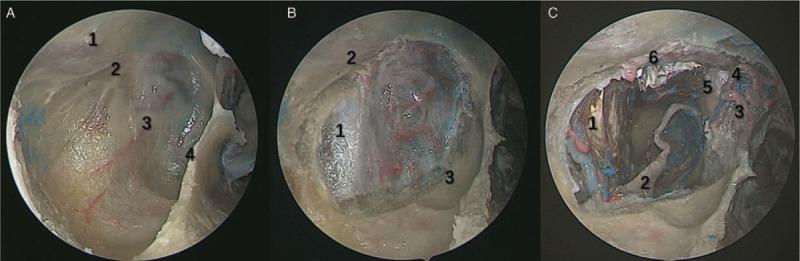

The endoscopic transnasal approach has been proven to have advantages on the removal of the tumors in pterygopalatine fossa (PPF) and infratemporal fossa (ITF). Herein, this study aimed to describe a modified approach for resection of the tumors in these areas, both in cadaveric specimen and clinical patients.

METHODS

The 20 adult cadaveric specimens and five patients with tumors in PPF and ITF were enrolled in this study. For the cadaveric specimens, ten were simulated anterior transmaxillary approach and ten were performed modified endoscopic transnasal transmaxillary approach. The exposure areas were compared between two groups and main anatomic structure were measured. Surgery was operated in the five patients with tumors of PPF and ITF to verify the experience from the anatomy. Perioperative management, intraoperative findings and postoperative complications were recorded and analyzed.

RESULTS

The modified endoscopic transnasal transmaxillary approach provided as enough surgical exposure and high operability to the PPF and ITF as the anterior transmaxillary approach did. The diameter of maxillary artery in the PPF was 3.77 ± 0.78 mm (range: 2.06-4.82 mm), the diameter of middle meningeal artery in the ITF was 2.79 ± 0.61 mm (range: 1.54-3.78 mm). Four patients who suffered schwannoma got total removal and one of adenocystic carcinoma got subtotal removal. The main complications were facial numbness and pericoronitis of the wisdom tooth. No permanent complication was found.

CONCLUSIONS

With the widespread use of neuroendoscopy, the modified endoscopic transnasal transmaxillary approach is feasible and effective for the resection of tumors located in PPF and ITF, which has significant advantages on less trauma and complications to the patients.

经鼻内镜入路已被证明在切除翼腭窝(PPF)和颞下窝(ITF)肿瘤方面具有优势。在此,本研究旨在描述一种改良的方法,用于切除这些区域的肿瘤,包括在尸体标本和临床患者中。

方法

本研究纳入了 20 具成人尸体标本和 5 例 PPF 和 ITF 肿瘤患者。对于尸体标本,10 例模拟经前上颌窦入路,10 例采用改良经鼻内镜经上颌窦入路。比较两组暴露面积,测量主要解剖结构。对 5 例 PPF 和 ITF 肿瘤患者进行手术,验证解剖学经验。记录和分析围手术期管理、术中发现和术后并发症。

结果

改良经鼻内镜经上颌窦入路为 PPF 和 ITF 提供了与经前上颌窦入路相同的足够手术暴露和高操作性。PPF 中上颌动脉直径为 3.77±0.78mm(范围:2.06-4.82mm),ITF 中脑膜中动脉直径为 2.79±0.61mm(范围:1.54-3.78mm)。4 例神经鞘瘤患者均获得全切,1 例腺泡状腺癌患者获得次全切。主要并发症为面部麻木和智齿冠周炎。无永久性并发症。

结论

随着神经内镜的广泛应用,改良经鼻内镜经上颌窦入路对于切除 PPF 和 ITF 部位的肿瘤是可行和有效的,与传统方法相比,对患者的创伤和并发症更小。